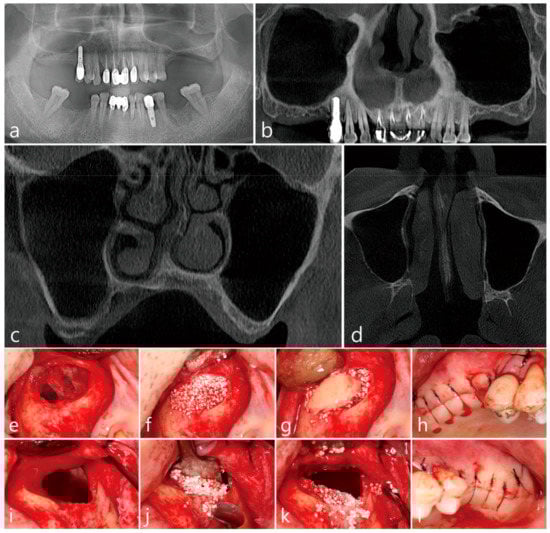

Maxillary sinus augmentation was performed on a 65-year-old male non-smoker with no reported systemic diseases. Panoramic radiographs revealed missing posterior maxillary molars. Subsequently, the left and right maxillary sinuses were pneumatized with resorption of the residual bone. CBCT revealed alveolar crestal height to be approximately 3 mm (Figure 2a) with a healthy Schneiderian non-compromised membrane, no thickening of the membrane was noted (Figure 2b). The lateral bone was noted to be thin without the presence of the posterior superior alveolar artery (Figure 2c,d). In the right maxillary sinus, sinus floor elevation via the lateral window approach was performed without the perforation of the sinus membrane, wherein, the lateral bone lid was removed (Figure 2e). The elevated sinus was filled with Osteon III (Genoss, Suwon, Korea) (Figure 2f), and the removed lateral bone lid was repositioned (Figure 2g). Flaps were closed (Figure 2h). In the left maxillary sinus, the lateral bone lid was removed, and subsequently, a large perforation of the Schneiderian membrane was observed (Figure 2i). In accordance with the proposed approach of the open lateral window technique (Figure 2j), the upper part of the lateral window site was left open after bone grafting (Figure 2k). The flap was closed at the lateral window site without membrane coverage (Figure 2l). Postoperatively, nasal bleeding and facial swelling were observed with eventual complete recovery, where no sinonasal complications occurred in the left and right maxillary sinuses. The patient underwent implant installation only in the right maxillary sinus 6 months after the maxillary sinus bone graft. A CBCT of the left maxillary sinus was acquired a year later (Figure 2m). Imaging revealed no membrane thickening and the exposed bone graft substitute was not covered with soft tissue (Figure 2n). No differences in membrane thickening of the left and right maxillary sinuses was observed. The volume of the implanted sinus bone graft had subsequently not changed, and the opened lateral window site was also filled with bone (Figure 2o).

Figure 2.

Case 2. Radiological findings of case 2. (a) On the panoramic radiograph before the procedure, pneumatization of the left and right maxillary sinuses and insufficient residual alveolar bone was observed; (b) Membrane thickening was not observed in the left and right maxillary sinuses on the panoramic image of the preoperative CBCT; (c) In the coronal image of the preoperative CBCT, the Schneiderian membrane was very thin and the buccal bone was not thick; (d) In the axial image of the preoperative CBCT scan, sinus membrane thickening was not found. Clinical picture of the lateral window approach with unintentional split-mouth design. (e) A lateral window approach performed in the right maxillary sinus without perforation of the Schneiderian membrane. After removal of the lateral bone window, the sinus membrane was separated from the sinus floor and elevated; (f) The MSA was performed. (g) The lateral bone window was repositioned; (h) The flap was closed; (i) An open lateral window approach performed on the left maxillary sinus with wide perforation of the Schneiderian membrane. The Schneiderian membrane was widely perforated during sinus floor elevation; (j) The Prichard elevator was placed in the maxillary sinus, and bone grafting was performed on the sinus floor; (k) After withdrawing the Prichard elevator, the upper part of the lateral window was opened. Membrane covering or repositioning was not performed; (l) The flap was closed. (m) Coronal image of CBCT immediately after the procedure. An open lateral window of the left maxillary sinus was observed; (n) Coronal image of CBCT 2 weeks after the procedure. The open lateral window was observed to close again. No leakage of the bone graft substitute was observed and there was no thickening of the Schneiderian membrane; (o) Coronal image of CBCT 1 year after surgery. An implant was placed in the right maxillary sinus, and an implant is scheduled to be installed in the left maxillary sinus. Membrane thickening was not observed. There was no additional leakage of bone graft.